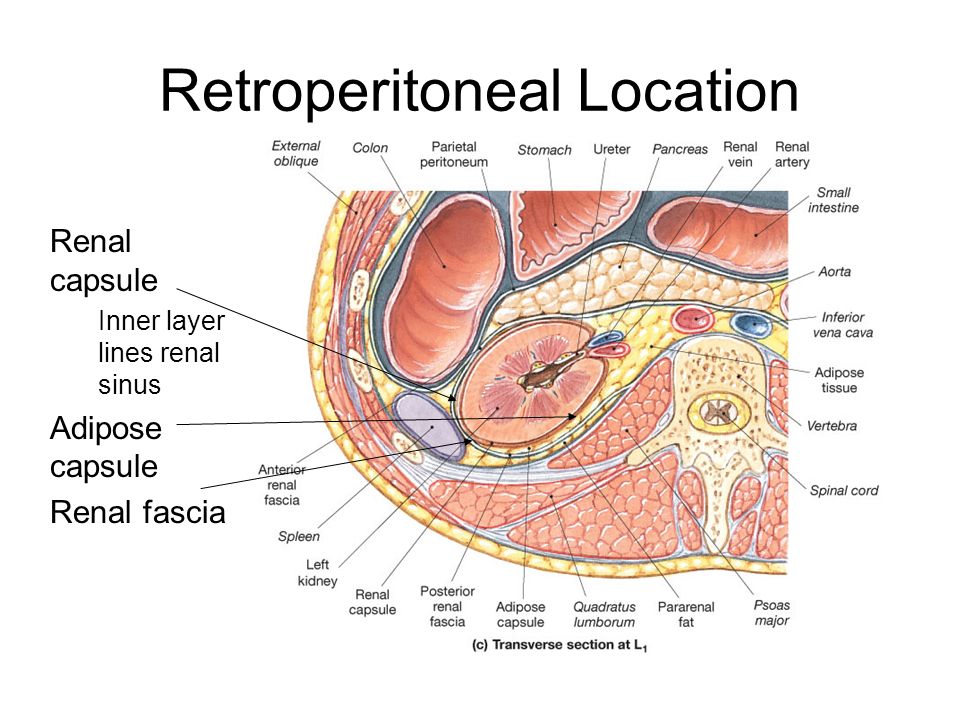

КТ ретроперитонеального фиброза: Изображения и диагностика